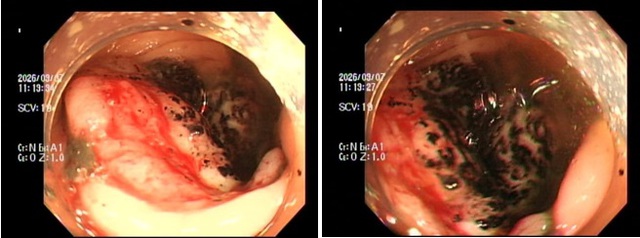

Hình ảnh qua ngã nội soi đại trực tràng. (Ảnh: BVCC)

Trường hợp đầu tiên là P.V.P.U (sinh năm 1991) đến khám chỉ vì... ông xã thấy dạo này da dẻ quá xanh xao. Bản thân U thỉnh thoảng cũng cảm thấy đau bụng nhẹ, thoáng qua nhưng lại tặc lưỡi bỏ qua vì nghĩ là rối loạn tiêu hóa thông thường. Khi thăm khám, bác sĩ phát hiện chị bị thiếu máu nặng. Ngay lập tức, chị được chỉ định nội soi đại tràng, kết quả khiến cả hai vợ chồng sững sờ: Có một khối u lớn ở đại tràng phải, bề mặt loét và rất dễ chảy máu, kết quả mô học khẳng định: Ung thư đại trực tràng.

Trường hợp thứ 2 là anh N.H.H.H (sinh năm 1995) đến viện với dáng vẻ mệt mỏi rã rời, than phiền hay bị chóng mặt kèm theo rối loạn đi cầu. Cứ nghĩ do làm việc quá sức, nhưng kết quả xét nghiệm lại báo động tình trạng thiếu máu nặng. Bác sĩ cho tiến hành nội soi đại trực tràng và phát hiện một khối u dạng vòng nhẫn đang chảy máu rỉ rả ở vùng trực tràng. Giải phẫu bệnh một lần nữa gọi tên: Ung thư trực tràng.